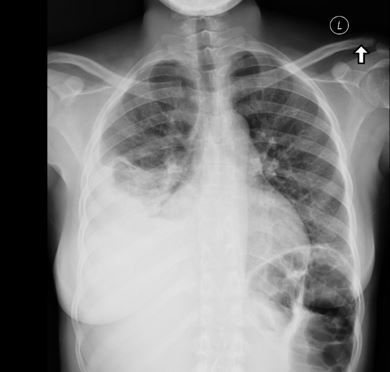

A chest radiograph showed a hyperinflated right lung with a shift of the mediastinal contents into the left hemithorax, suggestive of air trapping and consolidation in the right upper lobe and hilar region; there was no thymic shadow. A CT scan of the chest showed diffuse mediastinal and right hilar adenopathy; this caused partial compression of the right main-stem bronchus. MRI showed bilateral pleural effusion with hilar lymphadenopathy and mediastinitis. Examination of bronchial alveolar lavage fluid by PCR and culture was positive for Mycobacterium tuberculosis.